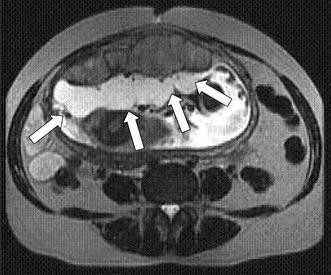

Delayed placental calcification maternal diabetes rh sensitization accelerated placental calcification norma. Often the lesion is associated with excessive x cell proliferation and cyst formation figure 275. And such are most often associated with pre eclampsia particularly the hellp syndrome variety hemolysis elevated lfts low platelets with rbc fragments. Placenta maternal floor infarction.